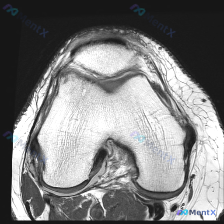

这是一张膝关节矢状位T1加权序列MRI影像,用户提出问题:观察图像是否存在软骨异常。

- 骨骼结构:股骨远端、胫骨近端、髌骨皮质连续,骨髓信号未见异常高低信号,关节面形态基本正常

- 半月板:形态信号正常,未见明显撕裂征象

- 交叉韧带、髌腱、股四头肌腱:走行连续,信号均匀,未见明显损伤表现

- 关节腔与软组织:无明显异常积液,髌下脂肪垫、腘窝未见异常占位

- 当前层面未见明确软骨缺损、剥脱

- 软骨下骨区域未见异常低信号,无明确软骨下骨损伤表现